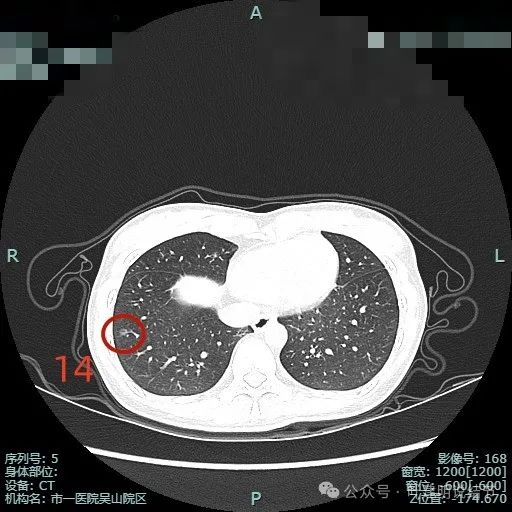

病灶14:右下叶磨玻璃结节,整体轮廓较清,有微小血管进入以及空泡征,考虑原位癌或不典型增生可能性大。